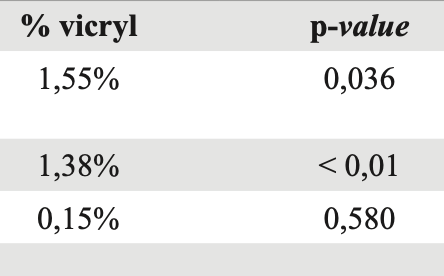

Katrina María Lolas Tornquist, Gabriela Smith Pedemonte, Agustín Gerardo Guerra Catalano, Gustavo Cwiklitzer Sumar, Percy Brante Baes

|

|